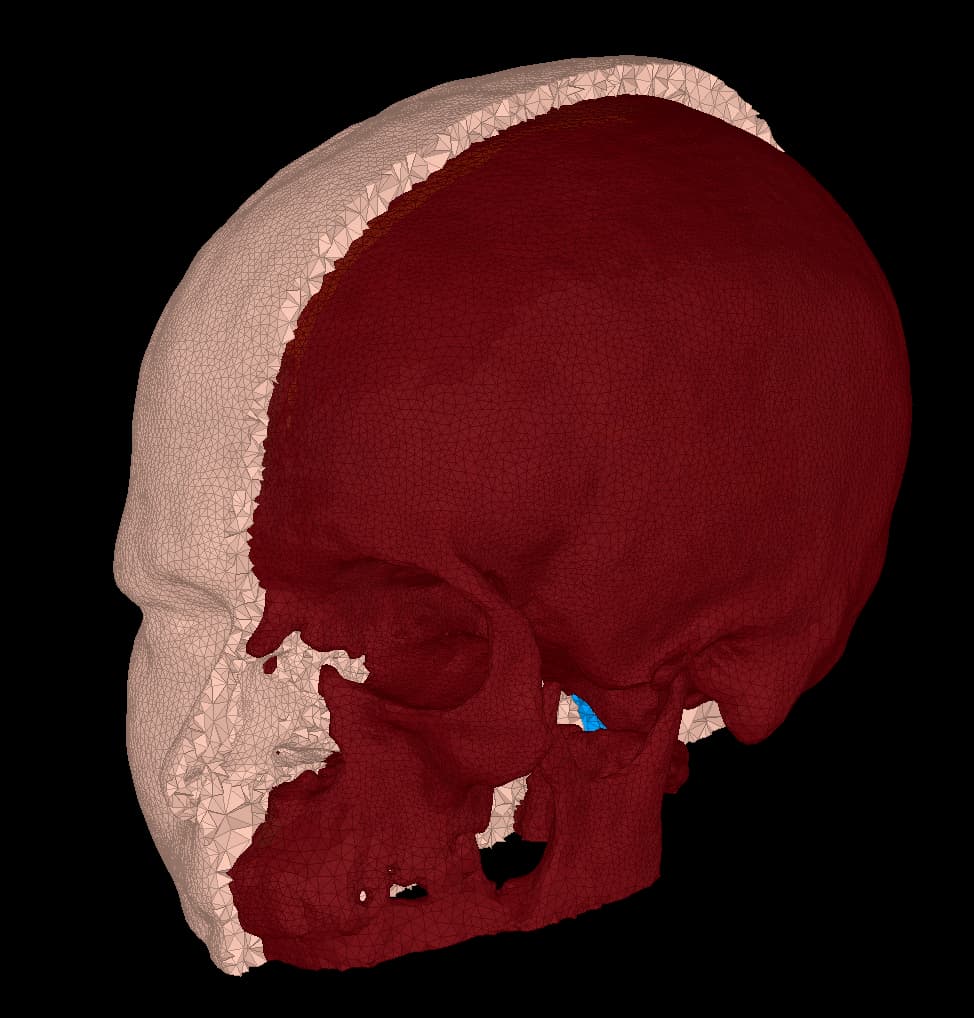

I am finding some quirky behaviour in the surface extraction tool from FEM model. When I display the FEM model, I obtain, for example, the right compact mask:

Then, I extract the surfaces, but what I now obtain as compact seems very different: